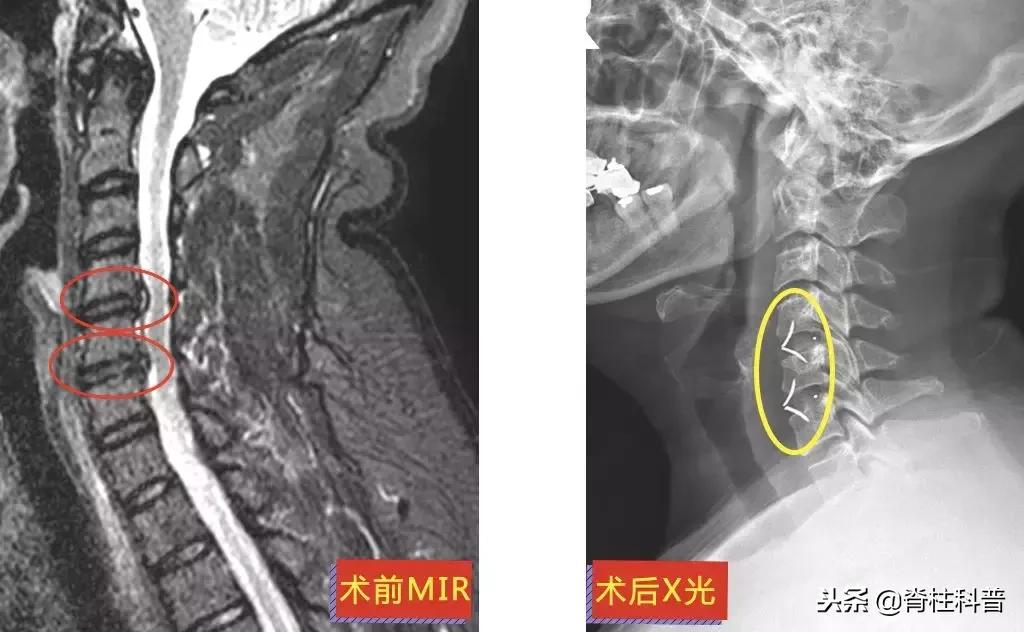

▲ 李三姨:术前MRI与术后X光

10天后,再次予以颈椎牵引治疗,症状稍缓解,可是颈痛发作频繁。经过熟人介绍,特意从茂名来到广州南方医科大学第三附属医院,找到张忠民主任医师治疗。在2018年9月20日在门诊被主任以“神经根型颈椎病”收治入院。10月3日手术,术后疼痛症状得到明显改善。